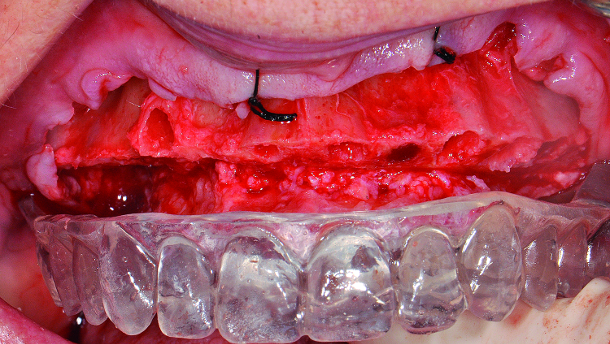

Starting with the maxillary arch, full-thickness flaps were raised and sutured to the buccal mucosa with 4-0 silk to provide improved surgical access and vision. The teeth were removed with the goal of buccal plate preservation using the PIEZOSURGERY (Mectron: Columbus, OH) for bone preservation (tips EX 1, EX 2, Micro saw: OT7S-3). The sockets were degranulated with PIEZOSURGERY (tip: OT4) and irrigated thoroughly with sterile water.

With the anatomically correct surgical guide in position and firmly held in place by the surgical assistant, measurements were made from the midbuccal of each tooth. Surgical cuts were made going from the anticipated cantilever of site #3 (FDI: #16) to site #14 (FDI: #26) using the PIEZOSURGERY saw (tip: OT7). Our team goal was to create the prosthetic room necessary for a hybrid restoration i.e. 10–12 mm. The cuts were intentionally extended beyond the anticipated cantilever length to create adequate strength and thickness of the final prosthesis in these unsupported cantilever areas (Figs. 5–6). The mandibular arch was treated in a similar manner. Additionally, bilateral mandibular tori reduction was accomplished with the aid of the PIEZOSURGERY saw (tip: OT7) after the extractions and prior to the vertical bone reduction of the mandibular ridge. Subsequently, the implants were placed.